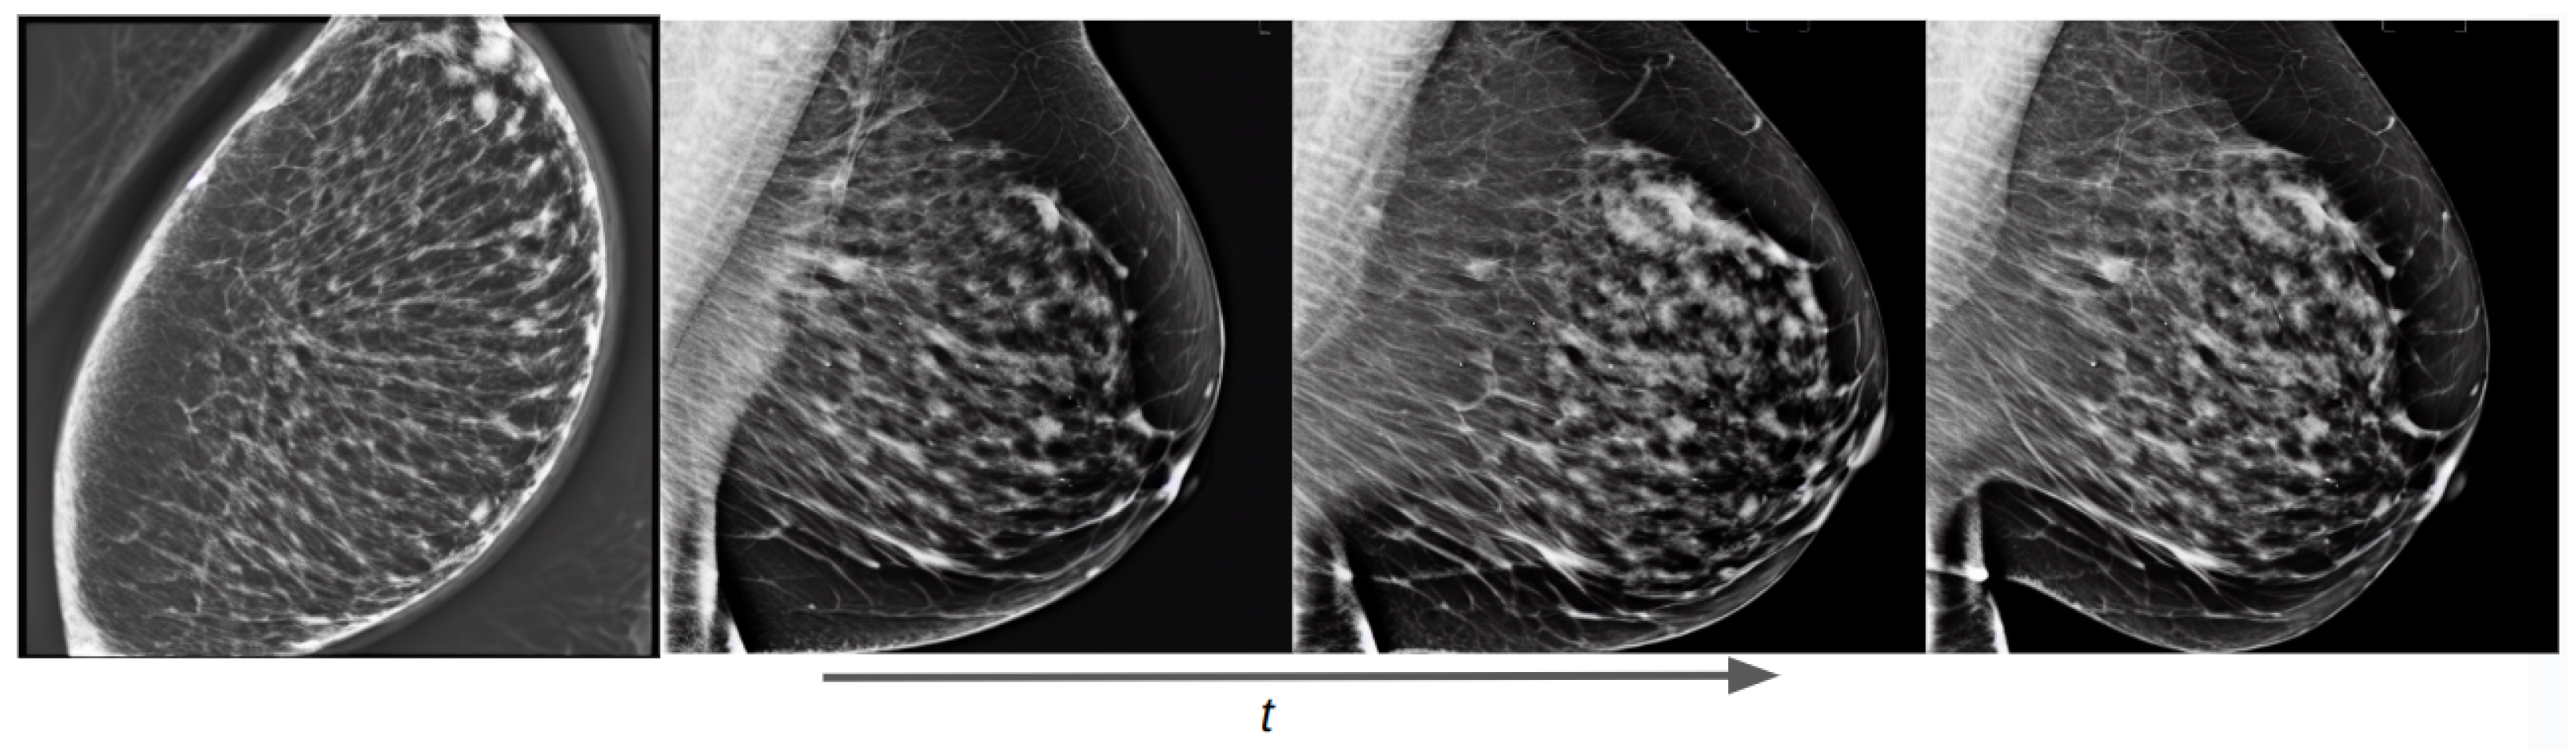

Figure 13.

Training evolution of SD with Hologic images at epochs 1, 3, 6, and 10. The prompt is: “a mammogram in MLO view with small area”.

Training examples of the two separate conditional models using prompt text are shown in Figure 13 for the OMI-H dataset and Figure 14 for the VinDr dataset. We observe that the fine-tuning technique allows the generation of meaningful images from epoch one. For the Hologic example, we can observe that, as the training process increases, the mammogram reduces its shape in accordance to the area described in the prompt text. Moreover, it can be noticed that our models differentiate the overall intensity appearance of mammograms, which is different between Hologic and Siemens systems.

Thanks to the combined fine-tuning of the CLIP text encoder and the UNet weights, our conditional models can learn the anatomical structure and form of a mammogram, and can also push the generated image in the direction of the text prompt semantics as the training process increases.